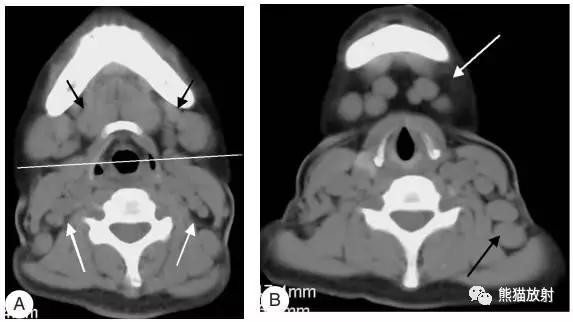

女性,45岁,淋巴瘤。(A)黑箭显示双侧IB区淋巴结,白箭显示ⅡA区淋巴结。(B)白箭显示ⅠA区淋巴结,黑箭显示左侧Ⅴ区淋巴结。

女性,45岁,淋巴瘤。黑箭显示双侧ⅡB区淋巴结。